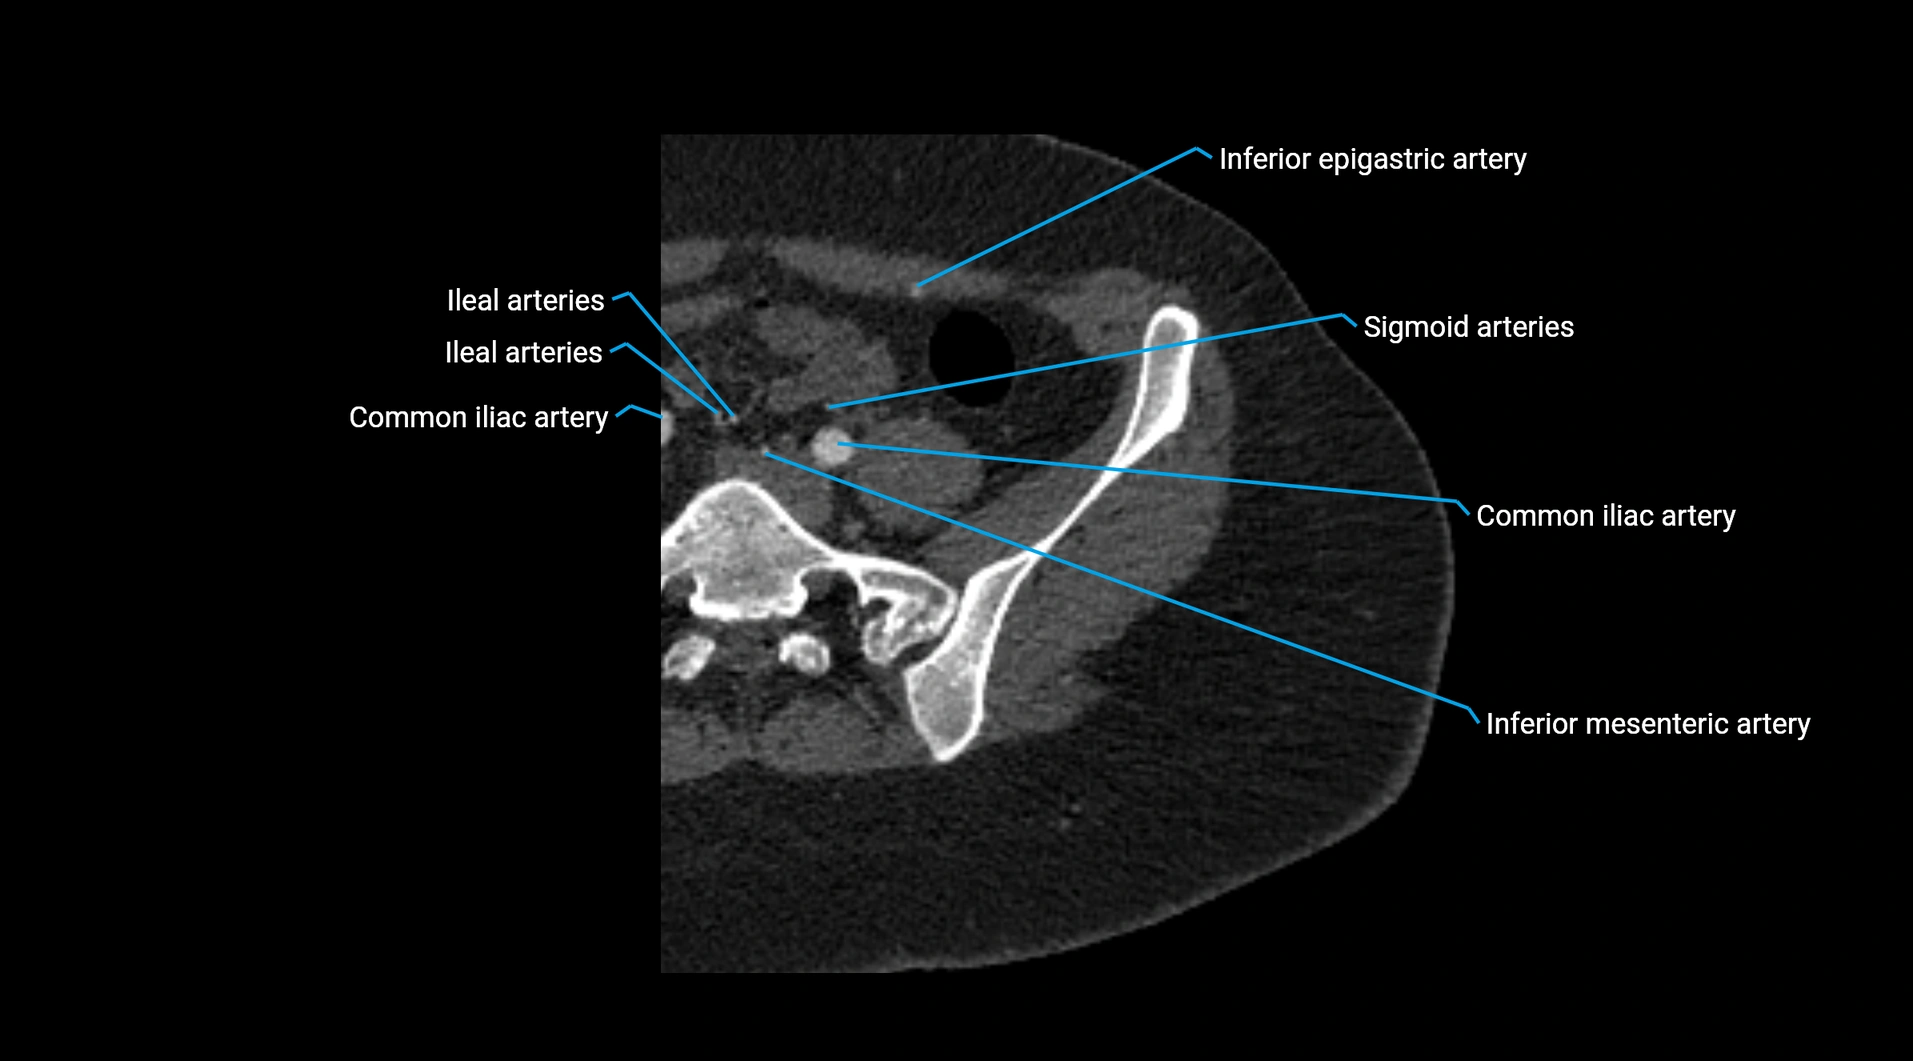

CT images

image

Contrast-enhanced CT (CTA):

• Gold standard for abdominal aortic imaging

• Provides excellent detail of lumen, wall, aneurysm, thrombus, and branch vessels

• Multiplanar and 3D reconstructions help in aneurysm measurement, stent graft planning, and dissection evaluation

• Unpaired visceral branches: celiac trunk, superior mesenteric artery (SMA), inferior mesenteric artery (IMA)

• Paired visceral branches: middle suprarenal arteries, renal arteries, gonadal arteries (testicular or ovarian)

• Parietal branches: inferior phrenic arteries, lumbar arteries, median sacral artery

• Terminal branches: right and left common iliac arteries